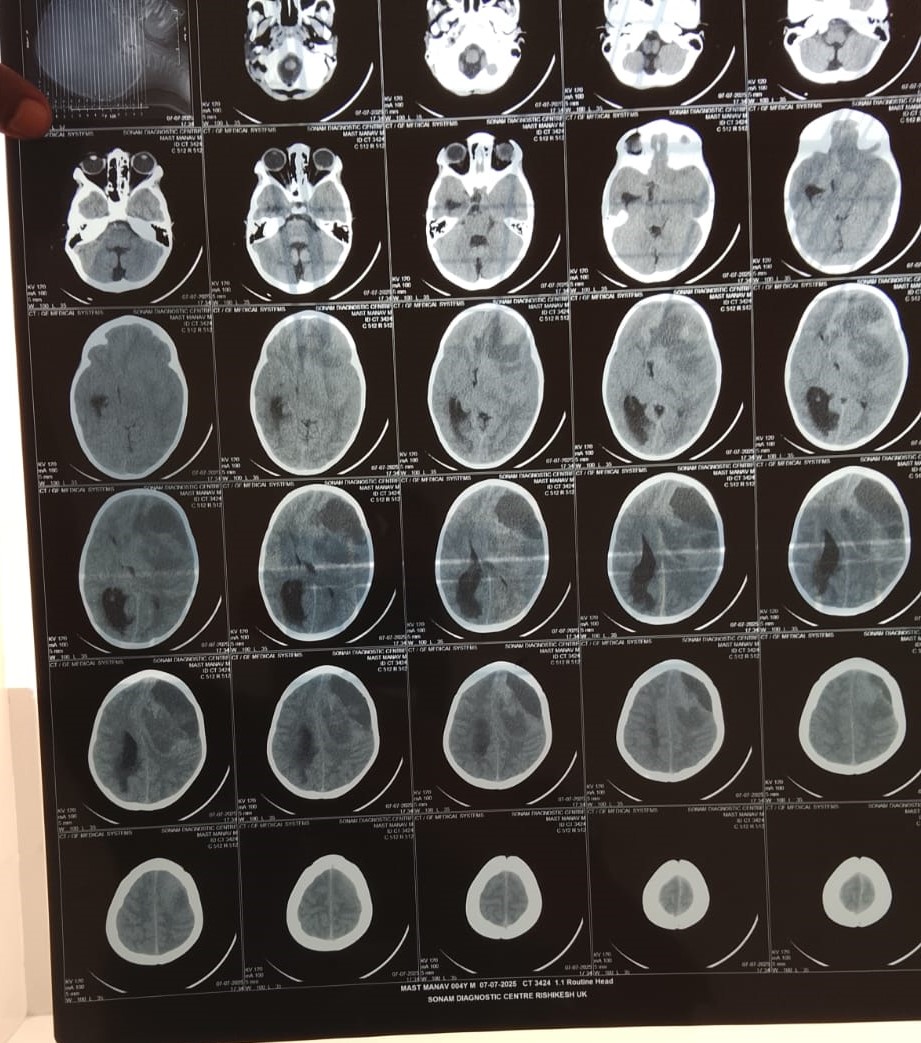

A Little Life Is in Danger – 4-Year-Old Manav Needs Your Urgent Help -We humbly appeal to your kindness and compassion to help save the life of Manav, a 4-year and 7-month-old child from village Sakni, Patti Bharpoor, Tehsil Devprayag, District Tehri Garhwal, Uttarakhand. Manav is currently battling a life-threatening brain tumor and is in critical condition.

Just a few days ago, Manav’s health started to deteriorate unexpectedly. He complained of severe headaches and vomiting. His parents took him for a medical check-up, and what followed was a devastating diagnosis — a large brain tumor that is causing swelling and pressure on his brain. Doctors immediately recommended urgent treatment, including brain surgery, with an estimated cost of ₹7 lakh.

Doctors at Jolly Grant Hospital, Dehradun, have advised immediate brain surgery, scheduled for 18th July 2025. Every hour matters now.